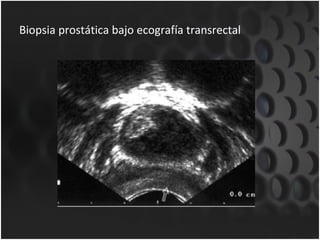

Biopsia prostática bajo ecografía transrectal Las limitaciones de la ETR para detectar el CaP consisten en que la mayor parte de las lesiones hipoecoicas halladas en la ETR no son canceres y el 50% de los canceres no palpables con un diametro mayor de 1cm no se observa en la ecografía 20-50% de los canceres pasan inadvertidos si solo se hace biopsia en las areas hipoecoicas

Biopsia prostática bajo ecografía transrectal Las aéreas hipoecoicas en la ETR tienen 2 veces mas probabilidades de contener cáncer en comparación con las aéreas isoecoicas. No sirve para localizar CaP temprano